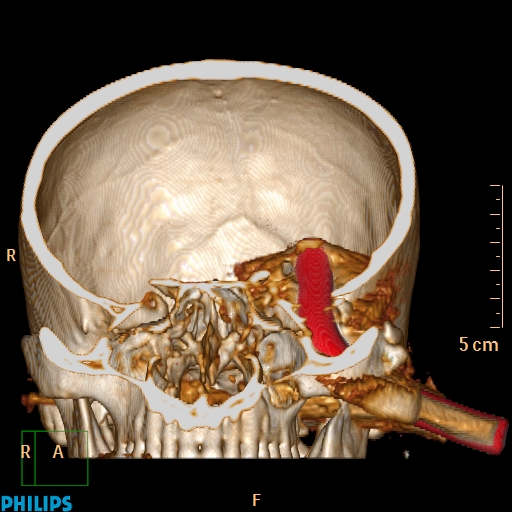

Accident de travail, chute sur une barre de fer. La barre de fer a été coupé sur le chantier pour dégager le patient A noter, comme on peut le voir sur la dernière image, que le patient était conscient et réveillé